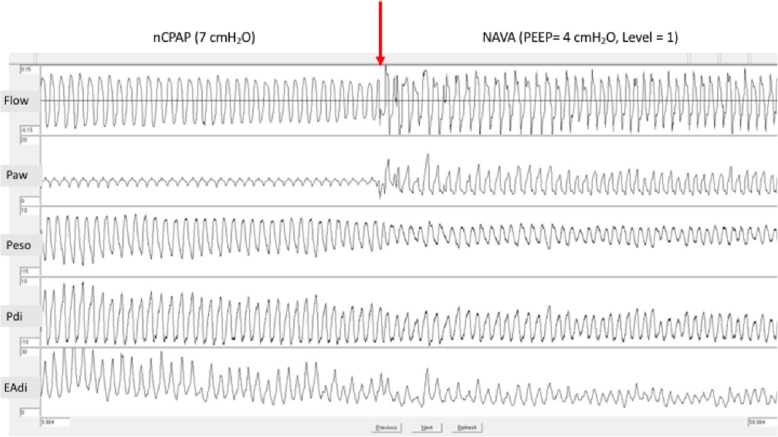

As detailed in Table 1 and illustrated in Fig. 1, all indices of WOB (PTPeso, PTPdi, ΔPeso, ΔPdi, Edi swing, and inspiratory time to total time ratio (Ti/Ttot)) decreased significantly in every child with NAVA as compared to nCPAP (p < 0.05 in all instances), while the mean Paw was increased (p < 0.05).

Fig. 1.

Decrease of esophageal and trans-diaphragmatic pressure swing and Edi amplitude after switching to neurally adjusted ventilatory assist. The red arrow indicates the switch from nCPAP to NAVA. nCPAP, nasal continuous positive airway pressure; NAVA, neurally adjusted ventilatory assist; PEEP, positive end expiratory pressure; Paw, airway pressure; Peso, esophageal pressure; Pga, gastric pressure; EAdi, electrical activity of the diaphragm

In this physiological study, we report an improvement of respiratory unloading by adding a second level of pressure with NAVA in infants with severe bronchiolitis. WOB decreased immediately after switching to NAVA (Fig. 1), as reported previously in adults with obstructive lung diseases [5], and was associated with a lower neural drive and Ti/Ttot ratio.